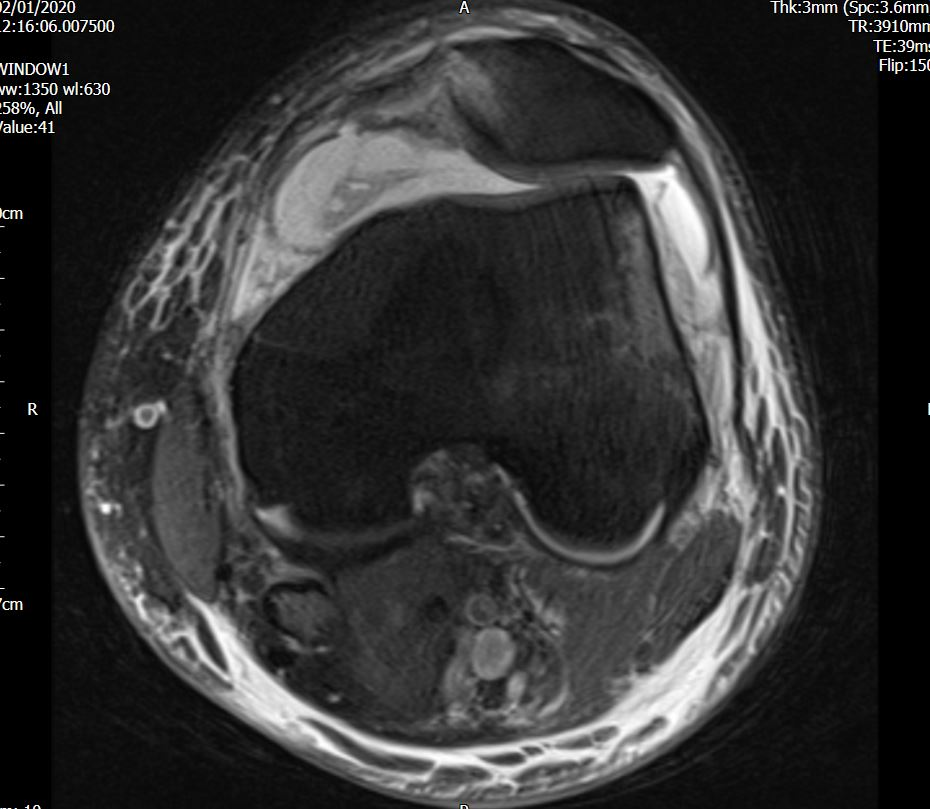

Computed tomography (CT) scan showed an OCF of the posterolateral femoral condyle (Figure 3 & 4). The MRI scan further confirmed the presence of an OCF of the lateral femoral condyle, and injury to the Medial Patellofemoral Ligament (MPFL), the latter is a secondary restraint to patella dislocation (Figure 5 & 6).

Figure 5 Axial MRI showing classical bruising pattern of patella dislocation & MPFL injury.